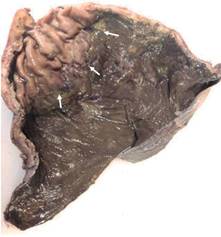

Paciente masculino de 69 años de edad con historia de diabetes mellitus tipo 2 en tratamiento con metformina y clorpropamida, hipertensión arterial en tratamiento con losartán y amlodipino. Se presenta al servicio de urgencias por mostrar cefalea, dolor torácico, tos, mialgias, artralgias y disnea de una semana de evolución. A su ingreso muestra frecuencia cardiaca 114 lpm, frecuencia respiratoria de 24 rpm, saturación de oxígeno de 80% sin apoyo de oxígeno suplementario, glucosa 587 mg/dl, leucocitos de 25,690 cel/mm3, neutrófilos 85%, linfocitos 1.2%, hemoglobina 16.3 g/dl, procalcitonina 3.78 ng/dl, gasometría arterial con pH 7.41, pCO2 21 mmHg, PO2 35 mmHg, HCO3 13 mmol/l, saturación de oxígeno 62%. Se realiza prueba rápida de antígeno para SARS-CoV-2 resultando positiva, tomografía axial computarizada (TAC) de tórax en la que se observan datos radiológicos sugestivos de infección por SARS-CoV-2 (Figura 1), se inicia manejo con oxígeno suplementario, bomba de infusión de insulina, carbapenémicos, antihipertensivos, dexametasona y profilaxis antitrombótica con enoxaparina. A las 48 horas de su ingreso continúa con choque séptico, se inician aminas vasopresoras, se realiza intubación orotraqueal y soporte con ventilación mecánica invasiva, se coloca sonda nasogástrica (SNG), la cual 24 horas posterior a su colocación reporta hematemesis acompañada de distensión abdominal, leucocitosis de 40,000 cel/mm3, se realiza TAC abdominopélvica simple, la cual revela neumatosis gástrica y neumoperitoneo (Figura 2), se efectúa laparotomía exploradora urgente encontrando necrosis de la curvatura mayor del estómago, se lleva a acabo gastrectomía vertical con engrapadora GIA cartuchos morados de 45 y 60 mm (Figura 3), se refuerza línea de grapeo con sutura continua prolene 00, se coloca sonda de yeyunostomía de alimentación a 60 cm del ángulo de Treitz y se dejan drenajes tipo Saratoga. A las 24 horas postoperatorias paciente reporta estabilidad hemodinámica y se suspenden aminas vasopresoras, se inicia nutrición enteral con dieta elemental. El quinto día postquirúrgico muestra adecuada tolerancia a dieta enteral por yeyunostomía, se realiza prueba con azul de metileno por SNG sin evidencia de fugas y descenso de leucocitos a 24,000 cel/mm3. Se recaba resultado de histopatología, el cual revela necrosis panmural asociada a trombosis arterial secundaria a microorganismos compatibles con Mucor sp., por lo que se inicia manejo con anfotericina B (Figuras 4 y 5). En el seguimiento muestra buena evolución, se realiza TAC abdominopélvica con contraste por SNG, la cual descarta fugas y colecciones intraabdominales y se corrobora integridad de la pared gástrica, se retiran drenajes y se da alta de cirugía general el día nueve postquirúrgico continuando manejo a cargo del servicio de medicina interna. Durante los siguientes días de hospitalización, el paciente presenta deterioro cardiovascular y pulmonar, se toma urocultivo, el cual evidencia crecimiento de Candida tropicalis, se realiza TAC de cráneo, tórax y abdominopélvica con contraste oral (Figuras 6 y 7), continúa sin evidencia de fugas a nivel abdominal, se descarta mucormicosis rinocerebral y pulmonar, se reporta probable neumonía bacteriana sobreañadida y neumopatía intersticial secundaria a COVID-19, persiste deterioro clínico y choque refractario, el paciente fallece a 29 días de su ingreso.

Figura 4: Pieza patológica con necrosis panmural asociada a trombosis arterial secundaria a microorganismos compatibles con Mucor sp.

Figura 5: Tinción con H-E en la que se identifica necrosis panmural asociada a trombosis arterial secundaria a microorganismos compatibles con Mucor sp.

La mucormicosis es una infección micótica invasiva con alta mortalidad, su incidencia ha aumentado en los últimos años debido al incremento de la población en riesgo de infección y la mejora en las herramientas diagnósticas. Fue descrita por primera vez a nivel pulmonar en 1876 por Furbringer.5 Ocurre principalmente en el contexto de un paciente inmunocomprometido.1 La mortalidad varía de 32 a 70%, la infección localizada se asocia con mejor supervivencia,6 se diagnóstica ante-mortem sólo en 25% de los casos. En su revisión de 31 casos, Dioverti y colaboradores reportan predominio en el sexo masculino (61%) y edad media de 47 años, 52% de los casos eran pacientes postrasplantados de órgano sólido y 35% pacientes en quimioterapia por neoplasia hematológica maligna, 100% de los pacientes presentaba al menos una comorbilidad, siendo la neutropenia la más común.2 Se ha descrito en pacientes con desnutrición severa, uso de corticoides, pero también en pacientes sin ningún factor predisponente.7 En nuestro caso el paciente tenía múltiples factores de riesgo ya descritos, la diabetes mellitus tipo 2 descompensada, la infección aguda por coronavirus y la terapia con esteroides que se inició para el manejo de COVID-19, como único factor que mejoraba el pronóstico se encontró la infección focal en estómago. La enfermedad se caracteriza por presentar vasculitis necrosante extensa con trombosis arterial e infarto tisular1 y presencia patognomónica de hifas ramificadas no septadas en ángulo recto en los tejidos,8 el género Rhizopus es el género que con más frecuencia se aísla.9 Entre los factores de riesgo conocidos se encuentra la hiperglucemia y la acidosis, ya que causan disfunción leucocitaria de neutrófilos y/o macrófagos afectando su quimiotaxis.10 Seis diferentes síndromes clínicos pueden presentarse, la infección rino-órbito-cerebral y la infección pulmonar son las más frecuentes y la gastrointestinal la menos común. Ésta se adquiere a través de la ingesta de alimentos contaminados o en el caso de cuidados asociados a la salud a través de dispositivos contaminados1 el estómago es el sitio más común de afección seguido del colon, intestino delgado y esógafo.11 La mayoría de los síntomas son inespecíficos, lo cual retrasa el diagnóstico y aumenta la mortalidad.2 La presentación clínica puede ser con dolor abdominal (68%), hemorragia gastrointestinal (48%), fiebre (19%) o cambios en la defecación (10%).2 A su ingreso el paciente no reportaba ninguna sintomatología a nivel abdominal, por lo que no existió ninguna sospecha de afección gastrointestinal, posteriormente se realizó sedación intravenosa e intubación orotraqueal siendo así imposible que el paciente manifestara afección a nivel gástrico, como único signo el paciente presentó hematemesis a las 24 horas de colocación de la SNG, lo cual descarta la posibilidad de una mucormicosis asociada a los cuidados de la salud, ya que 24 horas no son suficientes para lograr la introducción, inoculación y crecimiento del hongo, esto abre la hipótesis de que el paciente adquirió la infección micótica en su comunidad. El diagnóstico se puede sospechar por hallazgos endoscópicos, los cuales pueden ser una masa fúngica o lesiones necróticas que cubren áreas ulceradas que pueden perforarse y causar peritonitis.2 A menudo se inicia el protocolo de estudio ante la presencia de un absceso intraabdominal, el diagnóstico se puede efectuar mediante biopsia del área sospechosa durante la cirugía o endoscopia,7 pocas muestras son enviadas a cultivo2 y las que se envían son positivas sólo en 30%, además se requieren medios de cultivo especializados como agar papa dextrosa para favorecer el crecimiento de los hongos,12 se requieren además pruebas moleculares confirmatorias que pudieran detectar antígenos de superficie, los cuales aún no están disponibles.2 Los hallazgos por tomografía pueden ser los siguientes: engrosamiento focal o difuso de la pared gástrica, neumatosis con realce disminuido en la pared a la administración de contraste (gastritis enfisematosa) secundaria a la isquemia y necrosis, colecciones adyacentes, necrosis de la pared con disrupción focal o perforación y rara vez neumoperitoneo.13 Al presentar hematemesis estamos conscientes de que el siguiente paso diagnóstico podría haber sido una endoscopia digestiva alta, pero la distensión abdominal que presentaba el paciente sugería alta probabilidad de perforación de víscera hueca, por lo que inicialmente se realizó TAC de abdomen. Al reportar neumatosis gástrica y neumoperitoneo, se consideró una urgencia quirúrgica descartando la toma de endoscopia en ese momento, la laparotomía exploradora (LAPE) permitió la exploración directa del estómago y la resección parcial del mismo como medida diagnóstica y terapéutica. El tratamiento consiste en antifúngico y desbridamiento quirúrgico urgente, ya que la presencia de tejido necrótico afectará la penetración del antifúngico a los tejidos, además de lo anterior se deberá proporcionar soporte médico agresivo de las comorbilidades.14 La anfotericina B liposomal intravenosa es el tratamiento de elección, ya que ha demostrado ser más eficaz que la anfotericina B convencional,15 el retraso en el inicio de la anfotericina más de seis días aumenta al doble la mortalidad.4 A pesar de que la mayoría de la bibliografía sugiere el tratamiento quirúrgico agresivo, optamos por un tratamiento más conservador al preservar una porción del estómago efectuando solamente una gastrectomía vertical, ya que a la inspección macroscópica se presentaba delimitación clara entre el tejido necrótico y el tejido viable. Consideramos que el tratamiento quirúrgico que efectuamos fue acertado, puesto que en el seguimiento posquirúrgico el paciente mostró buena evolución, la prueba con azul de metileno y las dos tomografías de abdomen con contraste en estómago a través de SNG nos permitieron comprobar la integridad de la línea de sutura desde su primer día postquirúrgico y hasta el día de su fallecimiento, la muestra enviada a patología permitió efectuar el diagnóstico y así iniciar la terapia dirigida con anfotericina B, y ya que no se demostró afección fúngica por Mucor sp. a otro nivel orgánico, se atribuye la causa de muerte a las complicaciones infecciosas nosocomiales a nivel pulmonar y urinario.